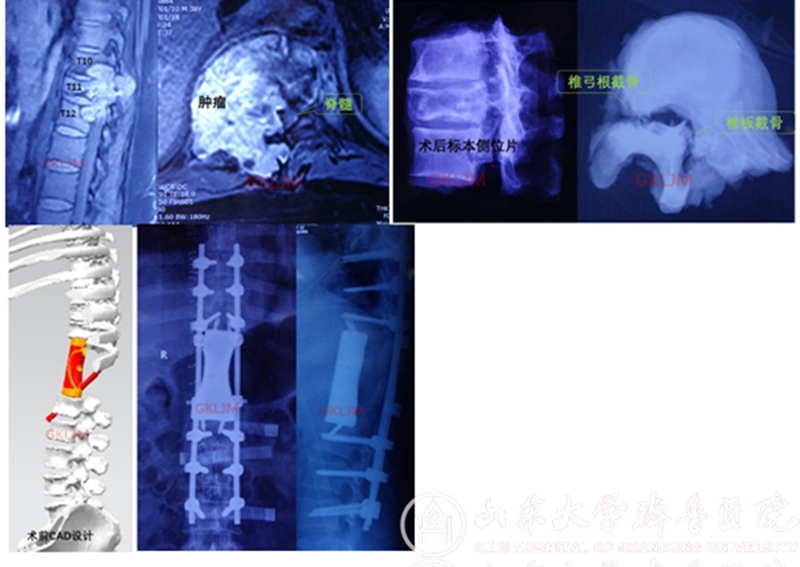

该患者因“双下肢疼痛、麻木1个月,无力10余天”来齐鲁医院就诊,之前曾在当地医院行穿刺活检,病理报告为低度恶性脊索瘤,因当地医院无能力切除肿瘤,患者慕名找到齐鲁医院骨肿瘤科李建民主任。当时患者已无法站立,处于截瘫的边缘,检查发现肿瘤累及第10-12三个胸椎,右侧椎旁形成软组织包块并侵犯膈肌,肿瘤侵入椎管压迫脊髓造成截瘫。

齐鲁医院病理科会诊考虑为软骨肉瘤,这是一种对放化疗等辅助治疗均不敏感的恶性肿瘤,手术彻底切除是唯一的希望。病情就是命令,时间就是生命,骨肿瘤科全体医护人员快速进行术前准备,医工结合定制3D打印人工椎体,营养神经治疗,联系输血科大量备血,请麻醉科会诊,请介入科术前行肿瘤供血动脉栓塞,请胸外科医师协助手术。

患者影像学检查

1月30日,经过充分术前准备后手术开始了,先在病椎上下各置入6枚椎弓根螺钉,切断并部分切除双侧6根肋骨,将脊椎一侧椎弓根打断,另一侧则经椎板截骨以减少肿瘤污染,整块切除后方附件,将三节段椎体绕过脊髓从右侧取出。李建民团队历时14个小时,克服了出血凶猛过万毫升的困难,顺利完成第10-12胸椎三节段切除,3D打印假体精准重建。术后患者恢复顺利,下肢感觉肌力逐渐好转。

3D打印即快速成型技术的一种,它是一种以数字模型文件为基础,运用粉末状金属或塑料等可粘合材料,通过逐层打印的方式来构造物体的技术,目前在各行各业中获得了广泛应用。而其在医学中的应用更是具有得天独厚的优势,常见的CT数据处理后即可得到打印数据,导入3D打印机即可打印出与原型尺寸、形状一致的模型,结合计算机辅助设计(CAD)技术可设计打印导板、内植物,更值得期待的是利用活的细胞作为打印材料直接打印有活性组织和脏器的生物打印技术。

由于骨肿瘤切除范围的不规律性和复杂性,经常面临骨关节缺损重建困难的问题,而3D打印的个体化定制恰恰满足了骨肿瘤切除重建精准、灵活的要求,在我院领导的支持下,借助于上海九院戴克戎院士的技术支持,骨肿瘤科积极开展了3D打印技术的临床转化应用,不但打印模型、导板,还设计打印金属内植物,已应用于脊柱、骶骨、骨盆、四肢等肿瘤切除后的重建,取得了良好的效果。